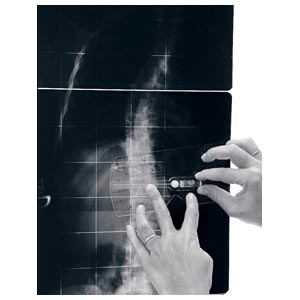

Strumento per la misurazione dell'angolo di Cobb e del gibbo. L'inclinometro è costituito da 1 elemento quasi-rettangolare di plexiglas recante una scala goniometrica, al cui centro è posizionata una piccola asta libera di ruotare e recante una bolla; l'estremità libera dell'astareca l'indice di lettura per la scala goniometrica. Il lato più lungo del rettangolo presenta una rientranza per renderne più agevole l'applicazione sul paziente (nel caso in cui le spinose siano sporgenti).

L'inclinometro è uno strumento manuale, normalmente utilizzato in due situazioni cliniche: • nella misurazione dell'angolo di rotazione del tronco durante il test di anteroflessione • nella misurazione dell'angolo di Cobb sulle radiografie (sia in proiezione AP che LL), quindi sia nella scoliosi che nella cifosi/lordosi.

L'angolo di Cobb è dato dalla somma dei due angoli di inclinazione delle limitanti. La misurazione dell'angolo è più veloce del metodo tradizionale (è sufficiente accostare lo strumento alle vertebre limite e leggere il valore sulla scala graduata), non richiede strumenti aggiuntivi, non deteriora le radiografie, semplifica la misurazione eliminando quindi alcune possibili cause di errore.

Un vantaggio dell'inclinometro sugli altri strumenti è dato infine dalla possibilità di misurare sia l'angolo di rotazione del tronco (gibbo) sul paziente, sia l'angolo di Cobb sulle radiografie con un solo semplice strumento.